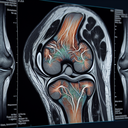

МРТ колінного суглобу

МРТ (магнітно-резонансна томографія) колінного суглоба – це неінвазивний метод діагностики, який використовує магнітні поля та радіохвилі для створення детальних зображень внутрішніх структур коліна. Цей метод дозволяє отримати чіткі зображення м'яких тканин, таких як зв'язки, сухожилля, меніски, хрящі та м'язи. **Переваги МРТ колінного суглоба**: 1...